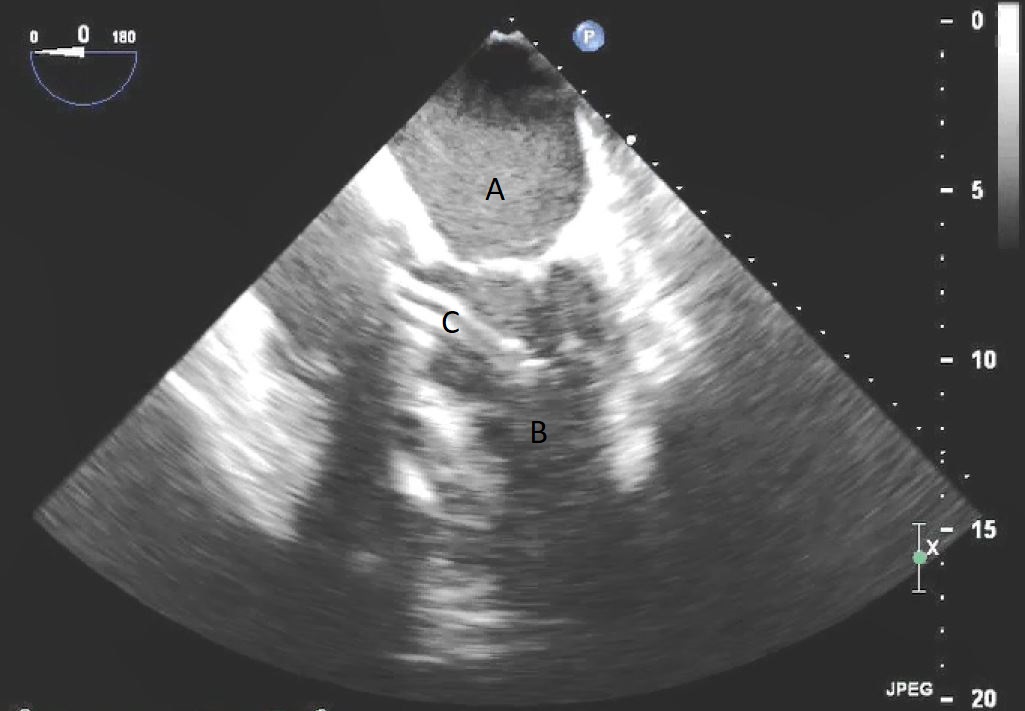

Fig. 1.TEE demonstrating IABP in descending aorta (A).

TEE demonstrating IABP in descending aorta (A) with reverberation artifact seen behind it upon activation (B).